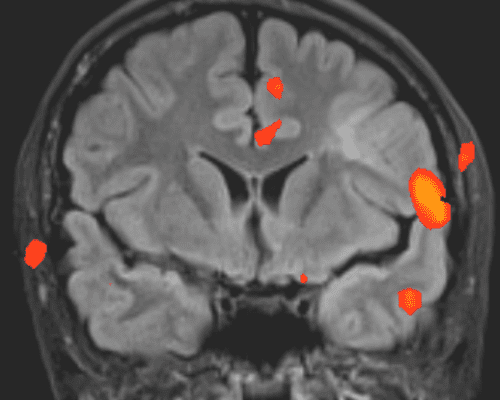

Tranzitorna (prolazna) globalna amnezija

Vrijeme čitanja članka: 2 minuteTranzitorna globalna amnezija je iznenadna, kratkotrajna epizoda gubitka memorije. Iako se smatra da je puno rjeđa od moždanog udara, bolesnici s takvom kliničkom slikom često se javljaju u hitnu neurološku ambulantu.